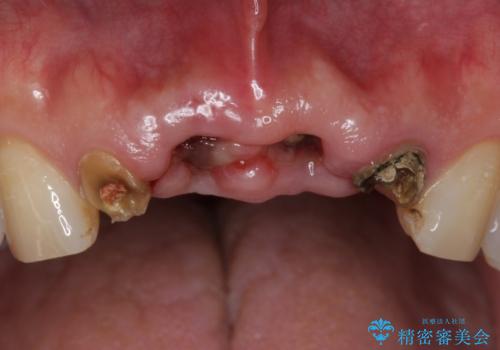

- お風呂場で転んで上の前歯が2本抜けてしまったことを主訴に来院された患者様です。

精査したところ、左上の側切歯(左上2)も破折しており保存不可能な状態でした。

左上の側切歯(左上2)を抜去し、右上の側切歯(右上2)の再根管治療後、セラミックのブリッジによる補綴を行いました。